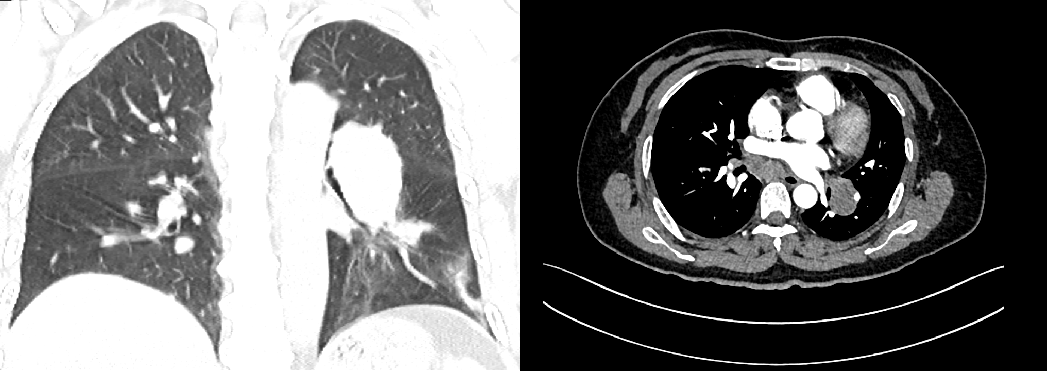

肺癌是严重威胁人民群众生命健康的恶性肿瘤,晚期肺癌患者已错失最佳手术时机,传统的化疗方案对于晚期肺癌患者的总体效果难以满足临床需求[1]。近年来,以PD-1/PD-L1抑制剂为代表的免疫疗法在肺癌治疗中的价值得到积极探索,我国自主研发的PD-1抑制剂替雷利珠单抗在肺癌领域也进行了广泛布局,目前已获批晚期非小细胞肺癌(NSCLC)一线及二/三线治疗适应症,且是唯一实现不可手术局晚及晚期NSCLC医保全程覆盖的PD-1抑制剂。 本期由中山大学孙逸仙纪念医院丁嘉萱医生为大家分享一例替雷利珠单抗用于晚期肺腺癌伴脑转移患者的诊疗过程,并由刘宜敏教授进行点评。该病例中,患者接受替雷利珠单抗治疗已实现超2年持续CR,目前免疫治疗已满两年,遂停止治疗,患者一般情况良好,后续定期影像学随访。 分享专家 丁嘉萱 医生 肿瘤学硕士 中山大学孙逸仙纪念医院放疗科医师 点评专家 刘宜敏 教授 病例详情 基本情况 一般情况:患者女性,53岁。 主诉:因“咳嗽伴气促4月,头痛半月”就诊。 现病史:患者咳嗽伴气促4月,头痛半月,于2020.05我院首诊。 既往史、个人史及家族史:无特殊。 月经婚育史:无特殊。 辅助检查 入院后基线评估: (1)胸部CT示:左肺门区可见一团块状影,大小约42.8mm*30.0mm,边界清,增强扫描呈轻度强化,强化尚均匀,病变包埋左下肺动脉,左肺下叶支气管狭窄,病变下缘可见子灶。纵隔内结构清楚,后纵隔内可见一团块状影,大小约52.8mm*21.0mm,边界清,强化方式与上述病灶相仿,与食管分界不清。双侧肺门淋巴结转移。 入院后胸部CT检查 (2)头颅MRI示:左颞叶、脑干见结节状稍长T1、稍长T2信号影,DWI呈稍高信号,增强后明显强化,周围见片状水肿影,直径分别为8.7mm和11.2mm;左颞叶、脑干异常信号灶,结合病史,考虑转移瘤;全腹MR和全身骨显像无明显异常。 入院后MRI检查 (3)超声支气管镜引导下的经支气管针吸病理活检(EBUS-TBNA):1、左上叶下舌段支气管及左下叶背段支气管,左下叶基底段支气管管腔外压性狭窄;2、隆突增宽;3、纵隔淋巴结转移(第7组,第11L组),EBUS-TBNA细胞病理提示为肺来源腺癌。 于左侧第二隆突探及第11L组淋巴结行EBUS-TBNA (4)免疫组化:TTF-1(+)、NapsinA(+)、CK7(+)、CK5/6部分(+)、Ki67约25%(+),P40(-),PD-L1(22C3)肿瘤细胞约30%(+)、PD-L1(22C3)免疫细胞约20%(+)。 (5)基因检测:RET基因重排。 临床诊断 左肺腺癌伴脑转移(T4N3M1c,IVB期);RET基因重排 诊疗经过 于2020.06.01、2020.06.22、2020.07.13、2020.08.04、2020.08.25、2020.09.15予替雷利珠单抗200mg+培美曲塞800mg+奈达铂110mg治疗6周期;期间于2020.06.04-2020.07.13行WBRT(37.5Gy/15f)+SRS(14Gy),WBRT同期给予替莫唑胺(75mg/m2)。 免疫治疗2周期后复查胸部CT提示:左肺门区肿块较前缩小(21*14mm),后纵隔淋巴结较前缩小(22mm*9mm),左颞叶病灶基本消失、脑干病灶明显缩小(5mm),水肿明显消退。疗效评估为PR。免疫治疗4周期后复查胸部CT,疗效达到CR。 治疗前vs. 免疫治疗2周期后复查胸部CT结果对比 治疗前vs. 免疫治疗2周期后复查胸部CT结果对比 治疗前vs. 免疫治疗4周期后复查胸部CT结果对比 后暂停免疫联合化疗,于2020.09.17-2020.10.30行肺癌累及野放疗(pGTV、pCTV:60Gy/30f)。后于2020.11.12-2022.08.25行替雷利珠单抗200mg+培美曲塞500mg维持治疗23周期。期间定期影像学随访(外院),疗效维持CR。 2021.11.17胸部CT提示:左肺下叶背段及左肺上叶近肺门区团片状密度增高影,其内支气管稍扩张,邻近胸膜可见增厚,同前大致相仿。右肺上叶纵隔旁至近肺门区亦见条片状实变影,部分沿支气管分布,局部支气管稍扩张;右肺中叶内侧段见少许条状影,同前大致相仿。少量心包积液较前稍增多,新见双侧胸腔少量积液。纵隔内见多枚小淋巴结。附见肝右叶后段低密度灶部分向外突出,肝脏余部另见低密度小结节,十二指肠降段见含气囊袋影,同前大致相仿。 2021.12.16头颅MRI(平扫+增强)提示:脑桥右侧区见一小条片异常信号影,T2W1及FLAIR上呈稍高信号,信号较前减低,T1W1上显示欠佳,增强扫描现片未见明确强化,余颅内脑组织形态、信号正常,中线结构居中,脑室系统形态、大小正常,脑池、脑沟及脑裂未见异常,小脑未见异常信号。增强后脑组织强化正常,未见异常信号灶。附见:双侧筛窦及右侧上颌窦黏膜少许增厚。 2022.06.23 PET-CT检查提示:1、左肺癌治疗后,左肺下叶背段及左肺上叶近肺门区斑片状密度增高影伴轻度代谢增高,病灶较前明显吸收,代谢较前减低,考虑放射性肺炎较前吸收、好转,建议追踪复查;2、左侧肺门(10L)及纵隔内(4R、5、7 组)多个小巴结,代谢未见明显增高,结合病史,考虑为淋巴结转移灶治疗后处于明显抑制状态,建议追踪复查;3、脑转移瘤治疗后,颅脑未见明显提示脑转移瘤的高代谢灶,结合病史,考虑脑转移瘤治疗后好转,请结合MRI增强结果。 患者接受免疫治疗满两年(末次治疗时间为2022.08.25),疗效维持CR,与患者充分沟通后,停止免疫维持治疗,定期随访。 2022.11.22头颅MRI(平扫+增强)提示:脑桥右侧区见一小条片异常信号影,T2W1及FLAIR上呈稍高信号,T2W1上显示欠佳,增强扫描未见明确强化,较前大致相仿。双侧顶叶及左基底节区异常信号灶。余颅内脑组织形态、信号正常,中线结构居中。脑室系统形态、大小正常,脑池、脑沟及脑裂未见异常。增强后余脑组织强化正常,未见异常信号灶。附见:双侧筛窦及上颌窦黏膜少许增厚。 2022.12.23胸部CT提示:双肺门区条片状实变影较前缩小、变淡,局部支气管通畅,增强扫描未见明确异常强化灶;右肺中叶内侧段见少许条状影,同前相仿。心包未见积液。纵隔及肺门未见肿大淋巴结;双侧胸腔未见积液。附见肝右叶后段低密度灶部分向外突出,最大横断面约4.4*2.5厘米,增强扫描呈早出晚归强化特点。肝脏余部另见低密度无强化小结节。十二指肠降段见含气囊袋影。 病程回顾 病例点评 该患者在完善相关检查后,最终被确诊为“左肺腺癌伴脑转移、后纵隔与双侧肺门淋巴结转移”。肺癌起病隐匿,约10%-25%的NSCLC患者在确诊时已发生脑转移,约50%的患者在疾病进展中发生脑转移[2]。肺腺癌作为NSCLC的主要病理类型之一,其发病率近年来持续上升[3]。 肺癌脑转移患者的死亡率很高,传统的治疗手段疗效非常有限。数据显示,在未接受治疗的脑转移患者中,中位OS仅为1个月,而接受最佳支持疗法的患者OS约为2个月[2]。近年来,免疫药物及靶向药物的研发问世,大大提高了肺癌脑转移患者的生存率。该患者PD-L1表达阳性,一项汇总分析结果显示[4],对于PD-L1 TPS≥1%的NSCLC脑转移(包括未经治)患者,相比单纯化疗,免疫治疗可改善治疗结局,同时具有更少的不良事件。 有研究表明[5],免疫联合放疗不仅可控制照射区原发肿瘤增殖,同时也能促进肿瘤组织释放抗原形成原位灭活疫苗增加免疫治疗疗效。在一项研究报道中,NSCLC脑转移患者接受免疫联合立体定向放疗安全性良好,不仅降低照射野外复发率,还可提高患者生存期[6]。此外,基因检测提示该患者存在RET基因重排,但我国首个高选择性RET抑制剂获批时间为2021年3月,在该患者2020年6月开始接受治疗时靶向药物暂不可及。 证据显示,免疫联合化疗具有协同增效作用[7],结合该病例具体情况及循证医学证据决定采用免疫联合化疗进行治疗。考虑到该患者为异地就医,为有效管理,提高患者依从性,需选择半衰期长的免疫药物,而我国自主研发的PD-1抑制剂替雷利珠单抗终末半衰期约为26天,达到同类药物最高范围,经MDT讨论予替雷利珠单抗联合化疗,并行WBRT+SRS(WBRT同期给予烷化剂)。近年来,替雷利珠单抗全面布局肺癌领域,积累了丰富的循证医学证据。 RATIONALE 304[8]为一项III期、多中心、随机、开放研究,旨在对比替雷利珠单抗联合化疗和单用化疗一线治疗晚期非鳞状NSCLC的疗效和安全性。在2022 ESMO IO大会上,RATIONALE 304研究公布了最新数据,中位随访16.1个月后,替雷利珠单抗联合化疗组的mPFS进一步延长至9.8个月,显著降低37%的疾病进展风险,ORR达到57.8%,其中CR率提升至4.9%,约为对照组的3倍;mDOR进一步提升至10.6个月,患者获益持久。同时,该研究在此次大会上首次更新了OS数据,联合治疗组的mOS达到21.6个月,HR为0.68,显著降低32%的死亡风险。此外,在RATIONALE 304研究[9]的事后分析中,首次探索了免疫治疗联合化疗的至缓解时间分布,旨在充分了解免疫治疗的反应特征、最大化免疫治疗的临床获益提供了全新思路。结果显示,替雷利珠单抗联合化疗治疗有近50%的应答者在第二次评估后(≥4周期治疗后)出现首次缓解,提示若首次肿瘤评估未达到肿瘤缓解,不必急于停药,继续治疗仍很有可能达到缓解;75%达到CR/PR的患者通过持续治疗,肿瘤会持续退缩,首次缓解到最大肿瘤缓解的中位时间为3.6个月(约5个周期),肿瘤缓解深度更深的应答者,其PFS有延长的趋势,提示已达到CR/PR的患者,持续治疗肿瘤可进一步缩小,实现更长PFS获益。 患者在接受替雷利珠单抗联合治疗2周期后快速达PR,4周期疗效达到CR。6周期后暂停免疫治疗,在针对肺癌累及野放疗后,继续予免疫联合化疗维持治疗23周期,考虑到患者耐受性,在保证疗效的基础上化疗药物(培美曲塞)由标准剂量减量至500mg,以提高生活质量,期间影像学随访疗效维持CR。该患者共接受替雷利珠单抗治疗29周期,截至发稿已实现超2年长生存,充分验证了其在真实世界中用于肺腺癌脑转移患者的有效性和安全性。 根据2020年V1版《NCCN 非小细胞肺癌临床实践指南》,如果患者一线应用免疫疗法,则应接受两年的免疫维持治疗[10],具体临床实践中免疫治疗满2年后继续用药也可持续获益。该病例中,患者自2020年6月开始免疫治疗,至2022年8月已满两年,与患者充分沟通后,停止免疫维持治疗。截至末次随访(2022年12月),患者一般情况良好,未来实现长期生存值得期待。 长期以来,生存期短、预后差的肺癌脑转移患者常被排除在临床试验之外,血脑屏障(BBB)及血液-肿瘤屏障(BTB)等特殊结构也给脑转移相关机制研究造成重重困难[2]。目前,免疫联合放疗还有许多亟待解决的问题,如疗效评价、治疗结合时机、放疗范围及剂量等[5]。期待在未来,该领域能有更深入的研究进展,造福万千肺癌脑转移患者! 参考文献: [1] 王渊, 谭盼, 等. 中国医院用药评价与分析. 2023,23(03). [2] 马力, 朱娅, 等. 中国医药导报. 2023,20(03). [3] 李芳, 韩采利, 等. 肿瘤防治研究. 2023,50(03). [4] Aaron S Mansfield, et al. JTO Clin Res Rep. 2021 Jul 1;2(8):100205. [5] 周冲, 韩亮, 等. 中华转移性肿瘤杂志,2022,05(4):340-343. [6] Kamran A Ahmed, et al. J Neurooncol. 2017 Jun;133(2):331-338. [7] 赵景景, 李玲, 等. 实用癌症杂志. 2022,37(06). [8] Shun Lu, et al. ESMO IO 2022: 138P. [9] Lu S , et al. CSCO 2022. [10] NCCN Guideline NSCLC 2020.V1.